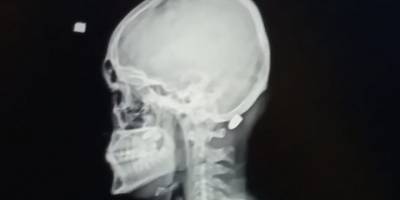

Trabzon'da havaya ateş etme geleneği can yakıyorTrabzon'da havaya ateş etme geleneği can yakıyorTrabzon'da havaya ateş etme geleneği can yakıyor